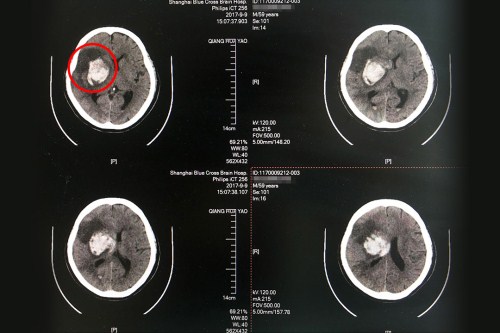

术前CT:右侧基底节区大量出血,血肿破入脑室系统,右侧高颅压。